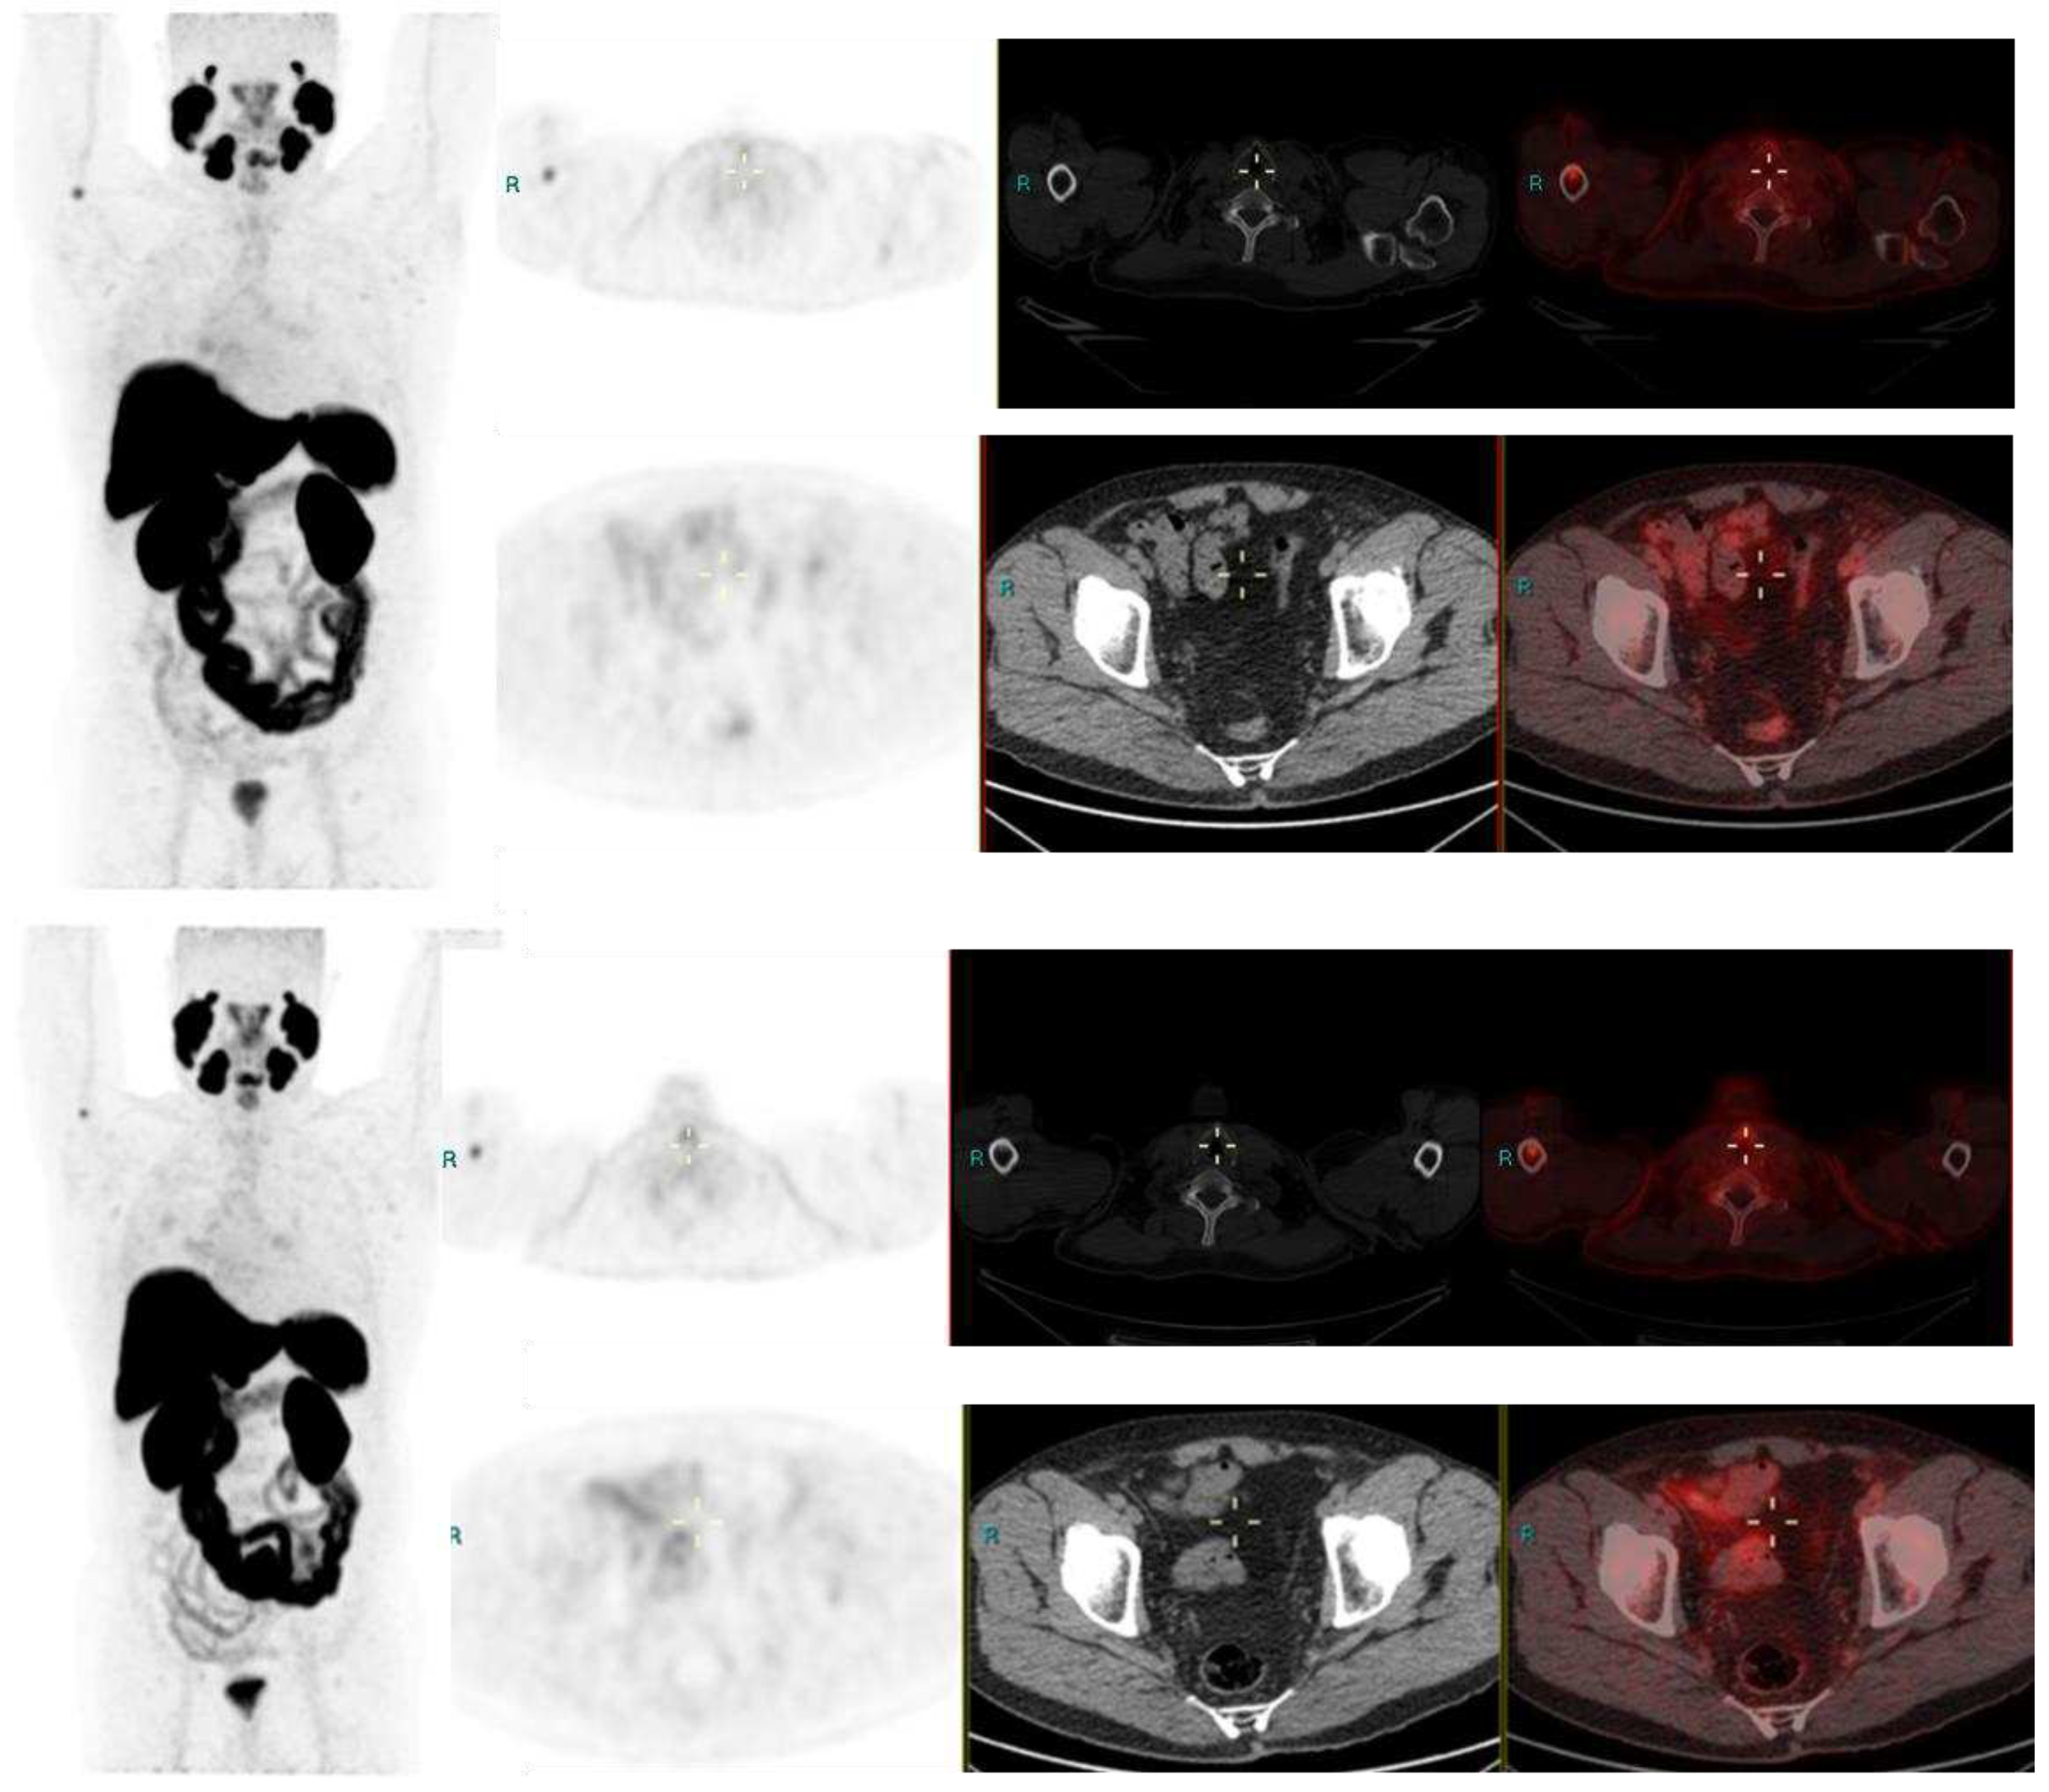

Image 1. Radical Prostatectomy - Negative scan at PSA 2.1 and 3.4 ng/ml, PSA rise of 1.3 ng/ml in after 6 months. PSMA RADS 1 B, due to uptake in prior known humeral fracture.

Image 2. Radical Prostatectomy negative scan at PSA 3.5 ng/ml, indeterminate lymph node at PSA 6.5, rise of 3ng/ml in 2 years RADS 3A – RP status. Consolidation in right upper lobe. Resolved on follow up CT after 2 months.